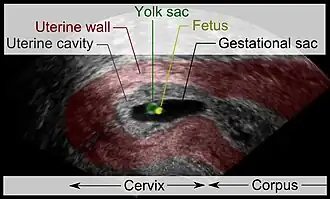

| Vaginal ultrasonography of a cervical pregnancy at a gestational age of five weeks. See image below for details of the visible structures.[1] | |

The diagnosis is made in asymptomatic pregnant women either by inspection seeing a bluish discolored cervix or, more commonly, by obstetric ultrasonography. A typical non-specific symptom is vaginal bleeding during pregnancy. Ultrasound will show the location of the gestational sac in the cervix, while the uterine cavity is "empty". Cervical pregnancy can be confused with a miscarriage when pregnancy tissue is passing through the cervix.